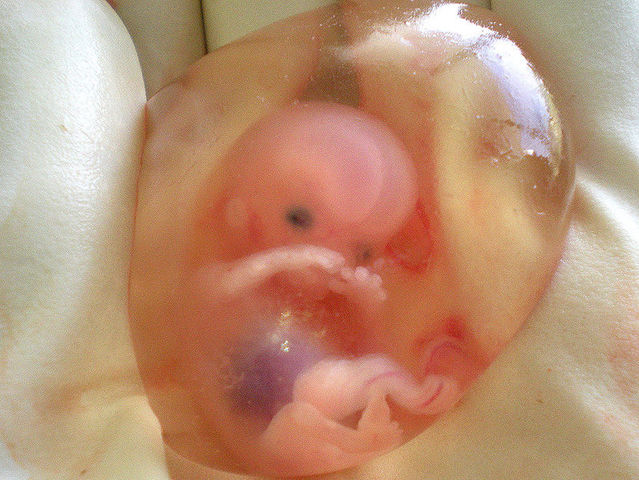

• 7 weeks

7 weeks

photo of thumb sucking

• 8 weeks

8 weeks

all body system present